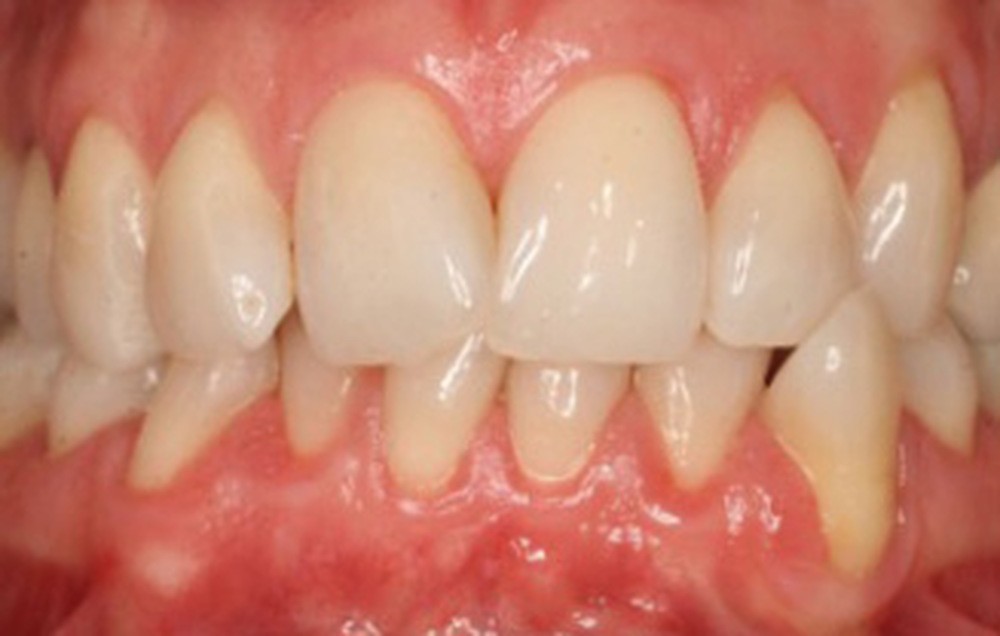

Quelle insatisfaction et quelle déception de constater, en cours ou à l’issue d’un traitement orthodontique, la fragilisation du parodonte, voire l’apparition d’une récession gingivale !

Le plan de traitement était-il le bon ? Fallait-il renforcer les tissus de soutien de la dent de manière préventive ?

C’est à ces questions que nous permettront de répondre les deux premiers conférenciers, parodontologistes : le Dr Béatrice Straub nous présentera le renfort parodontal minéralisé, technique qu’elle a développée et pratique depuis de nombreuses années, pour éviter les préjudices des mouvements orthodontiques à risque, notamment lors des décompensations préchirurgicales (fig. 1a-d) ; le Pr Anton Sculean abordera le thème des greffes, avec leurs indications, les différentes techniques à privilégier et illustrera ses propos par de nombreux cas cliniques aux résultats esthétiques impressionnants.